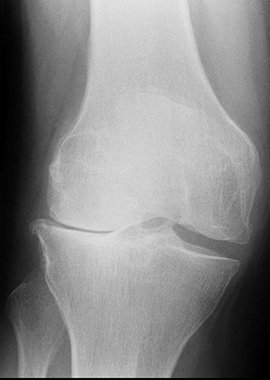

Generell sind bei Arthrose die Therapieoptionen zur Modifikation des Krankheitsverlaufs äußerst limitiert mit spärlicher Evidenz lediglich für Glucosamin und Chondroitin in Bezug auf die radiologische Progression. Vor diesem Hintergrund erregen aktuell publizierte Daten US-amerikanischer Experten um Tuhina Neogi, Boston, große Aufmerksamkeit. So war bei Gonarthrose-Patienten das Risiko für einen Kniegelenkersatz (KE) bei Bisphosphonat (BP)-Anwendern um 25 % verringert – ein klinisch relevanter Unterschied. Pathophysiologisch betrachtet könnten antiresorptive Antiosteoporotika wie BP aber auch der RANKL-Inhibitor Denosumab positive Effekte auf den subchondralen Knochen ausüben, Hinweise darauf wurden in Studien bereits gefunden. Unklar ist, inwieweit daraus subsequente Effekte auf den Knorpelmetabolismus oder strukturelle Veränderungen (Gelenkspaltverschmälerung, Osteophyten oder Knochenmarködeme) folgen. In der Summe hält Lems positive Effekte von BP (und Denosumab) auf die Progression der Gonarthrose für wahrscheinlich. (1)

Neogi und Kollegen griffen auf das „The Health Improvement Network“ (THIN) zurück, in dem von britischen Allgemeinärzten gesammelte Daten eingehen. Lediglich Patienten mit inzidenter Gonarthrose (im Mittel 76 Jahre) wurden eingeschlossen und 2.006 Fälle, die mindestens ein Jahr nach der Diagnose eine BP-Therapie begonnen hatten, ebenfalls 2.006 mittels Propensity-Score gematchten Fällen ohne BP-Einnahme gegenübergestellt. Nach einem mittleren Follow-up von drei Jahren betrug die krude Inzidenz von KE 22,0 pro 1.000 Personenjahre (PJ) bei BP-Anwendern versus 29,1 bei Nicht-BP-Anwendern (Hazard ratio, HR 0,74; 95% KI 0,59-0,93), die BP-Einnahme war also mit einer Risikoreduktion um 26 % assoziiert. Auch nach sorgfältiger Adjustierung auf Einflussfaktoren blieb der Vorteil erhalten (HR 0,76; 95% KI 0,60-0,95) und wurde durch Sensitivitätsanalysen untermauert. (2)

In dieser Taiwan-weit durchgeführten Studie mit Gonarthrose-Patienten waren über 12.000 BP-Anwender mit 123.000 Nicht-BP-Anwendern verglichen worden. Mit 25 % war die Risikoreduktion für KE (HR 0,75; 95% KI 0,69-0,83) fast identisch zu den THIN-Daten. Zudem zeigte sich hier eine Dosisabhängigkeit: Bei Patienten, die BP für ≥2 Jahre regelmäßig einnahmen (Adhärenz ≥80 %), betrug die Risikoreduktion sogar 34 % (HR 0,66; 95% KI 0,43-0,95). Überdies zeigte sich bei BP-Nutzern im 5-Jahres-Follow-up eine signifikant größere Reduktion im Gebrauch von NSAR, Paracetamol und Glucosamin (p<0,001). (3)